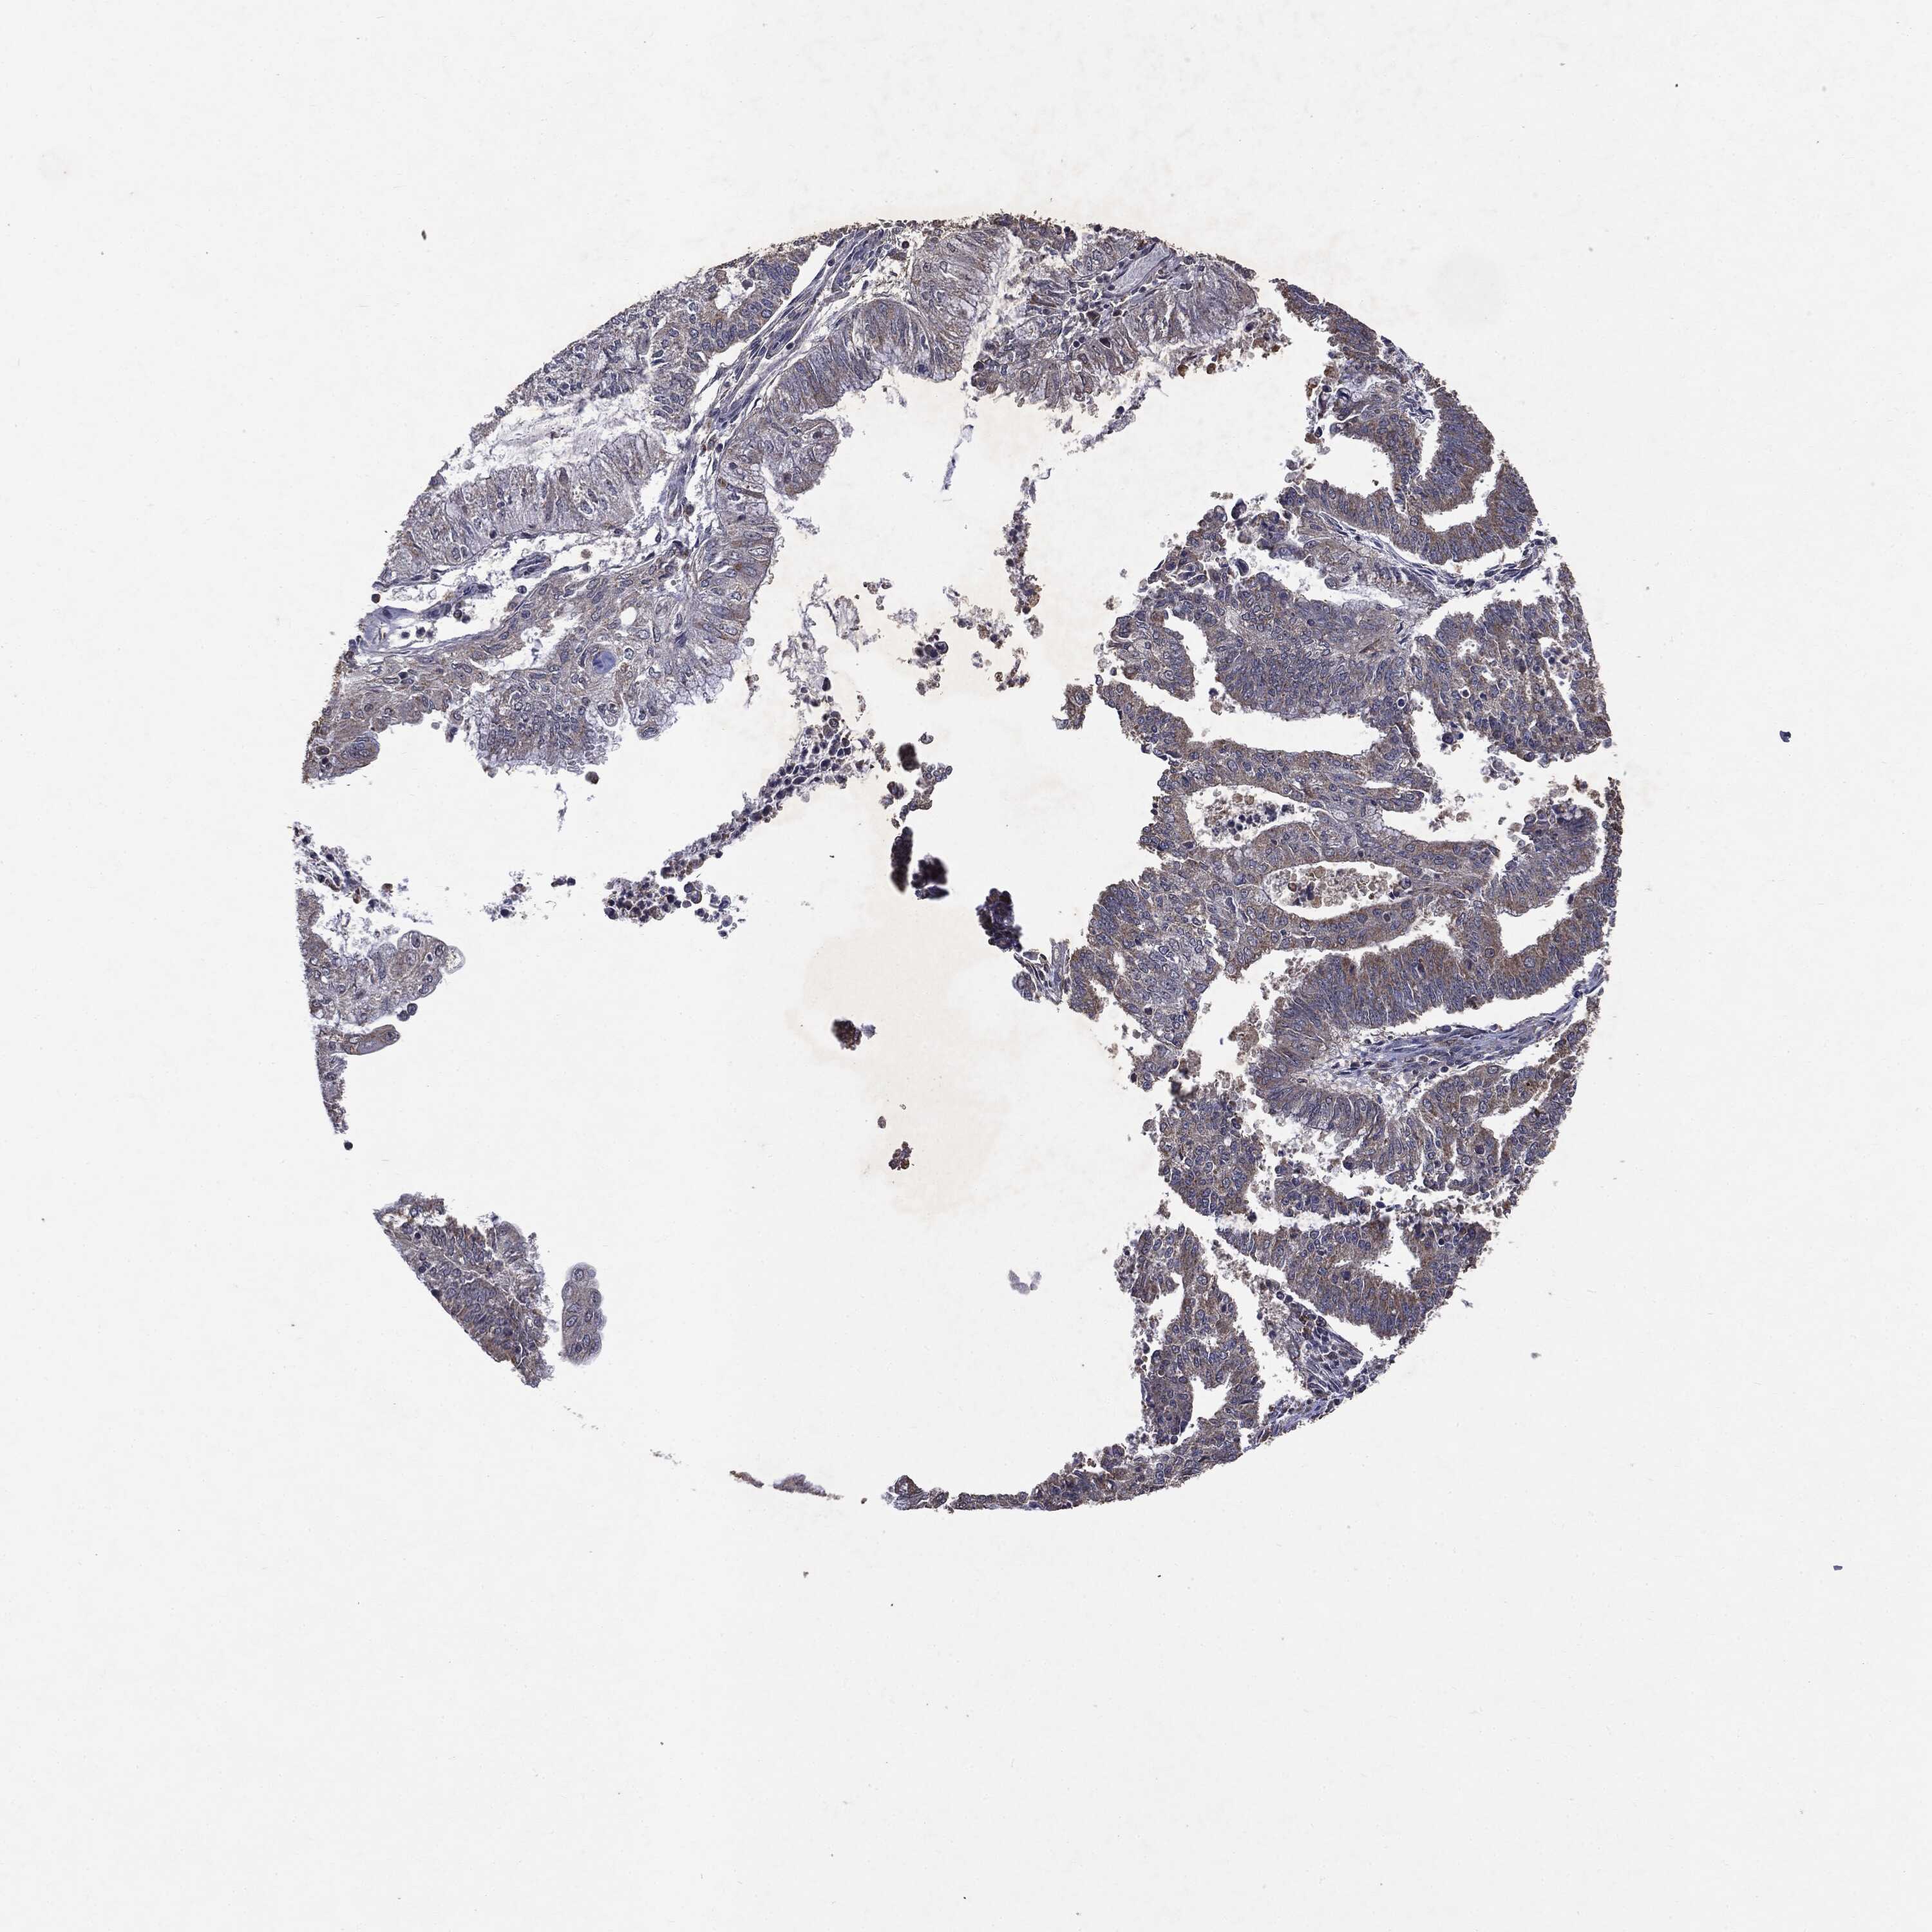

ENDOMETRIAL CANCER - Protein expressioni

A mouse-over function shows sample information and annotation data. Click on an image to view it in a full screen mode. Samples can be filtered based on level of antibody staining by selecting one or several of the following categories: high, medium, low and not detected. The assay and annotation is described here.

Note that samples used for immunohistochemistry by the Human Protein Atlas do not correspond to samples in the TCGA dataset.

Antibody stainingi

Antibody staining in the annotated cell types in the current human tissue is reported as not detected, low, medium, or high, based on conventional immunohistochemistry profiling in selected tissues. This score is based on the combination of the staining intensity and fraction of stained cells.

Each image is clickable and will lead to virtual microscopy that enables deeper exploration of all samples and also displays staining intensity scores, fraction scores and subcellular localization as well as patient and tissue information for each sample.

Antibody HPA031335

Antibody CAB004076

Antibody CAB080153

Antibody CAB080157

Staining

High

Medium

Low

Not detected

Intensity

Strong

Moderate

Weak

Negative

Quantity

>75%

75%-25%

<25%

None

Location

Nuclear

Cytoplasmic/membranous

Cytoplasmic/membranous,nuclear

Adenocarcinoma, NOS

Neoplasm, malignant, NOS

Carcinoma, NOS

Adenocarcinoma, metastatic, NOS